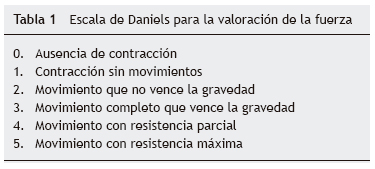

Al inicio de TRE, la valoración de rehabilitación mostró una deficiencia músculo-esquelética severa que limitaba la realización de actividades cotidianas y la participación social. Se apreciaron arcos de movilidad pasivos completos con fuerza de 2/5, en su mayoría en músculos del tronco y extremidades superiores, y de 1/5 en extremidades inferiores, según la escala de Daniels (tabla 1).

A los dos meses, se registró una mejoría notable en cuanto al sostén de tronco, sedestación y movilidad en extremidades inferiores, de acuerdo con la escala de Daniels, con fuerza muscular intrínseca y prono supinadores de 3; tríceps, bíceps, flexores y abductores de hombros de 2; flexores de cadera de 3, y extensores de rodilla, eversores, flexores y extensores de tobillo de 1 (tabla 2).

Hacia el tercer mes de TRE se logró el retiro de BiPAP intermitente, con oxígeno en puntas nasales. La paciente egresó para continuar con manejo ambulatorio, con tratamiento de hipertensión pulmonar con anticongestivo y vasodilatador pulmonar, así como manejo ventilatorio con BiPAP intermitente. La paciente tenía equilibrio de cuello y tronco, así como apoyo de manos. Evolucionó de posición acostada a sentada, con dificultad, desplazándose distancias cortas con arrastre, e iniciando alimentación independiente. Miembros superiores e inferiores aún limitados a la extensión de rodilla con regazo de 30°. La fuerza muscular fue evaluada con escala de Daniels (tabla 1) en miembros superiores (bíceps, prono-supinadores y mano en 3, resto 2, fuerza en miembros inferiores en 2).